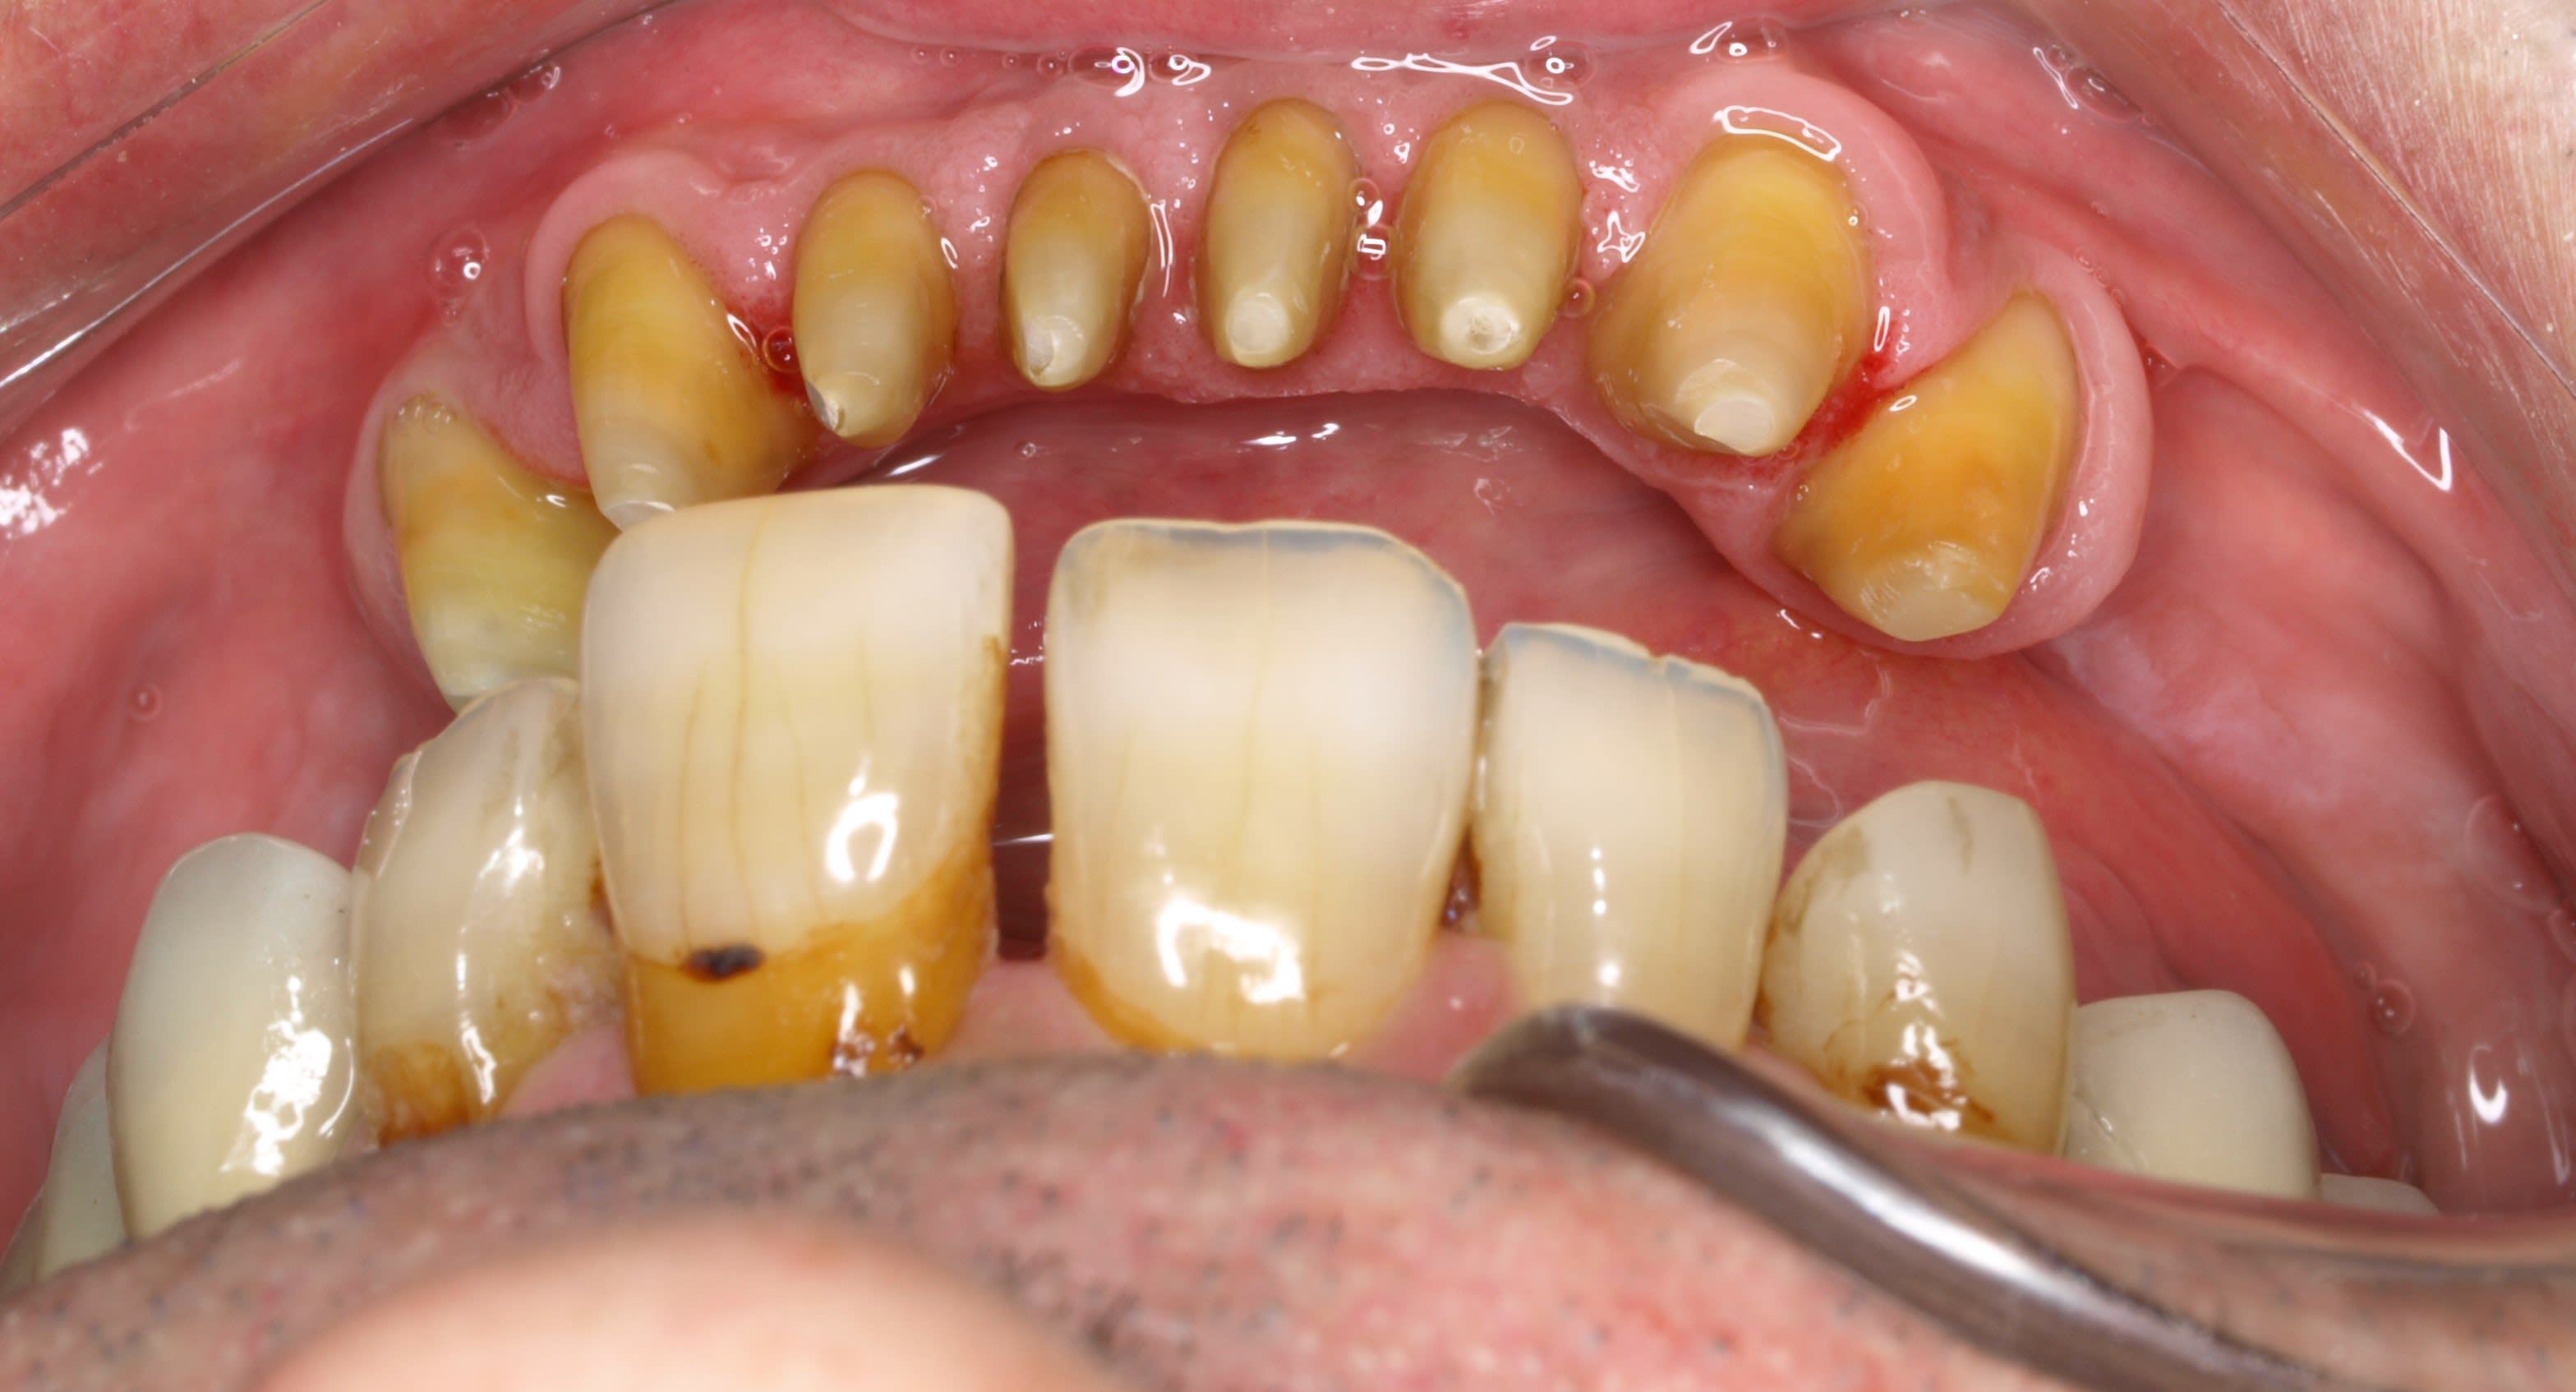

comme ça .

cas n° 3 : dit le coup à la ouane eugaine more

à l américaine si tu préfères . sais plus dans quel état il a fait ça peut être dans un état proche de l Ohio .

alors on lui a fait des facettes en haut et bas et plein de couronnes derriere . si je te dis le tarif , tu te pends la corde accrochée au scialytique en sautant par la fenêtre .

a force de lui recoller ses facettes du bas en urgence , je lui ai conseillé de retourner voir son ricain qui lui a couronné de 33 à 43 .

t as vu comme c est moche ? ses dents du bas sont petitounes en forme de bonbon acidulé en sur occ , trop en arriere , et pour chercher de la rétention ça a été taillé trop profond .

la sur occ + le taillage profond = paro